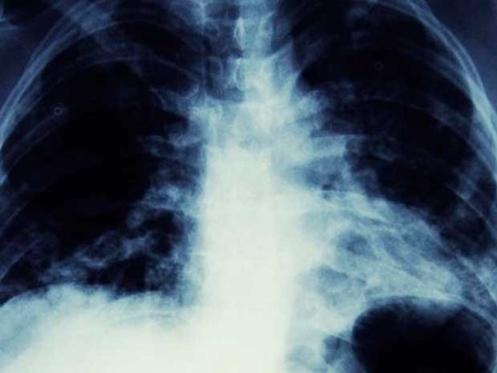

Las radiografías de tórax, mostraban una terrible mancha negra en su pulmón izquierdo, lo que era interpretado como un posible cáncer; sin embargo, además de la tos, no había más signos que indicaran que en realidad se trataba de esta terrible enfermedad.

Resulta que la mancha negra se trataba de un pequeño cono de tráfico de 'Playmobil' que le habían regalado en su cumpleaños número 7.

Los médicos sorprendidos no podían creer que el objeto hubiera vivido en su interior durante 40 años: “Finalmente encontró su cono perdido de Playmobil en el último sitio en el que se le hubiese ocurrido mirar”, decía el informe médico.